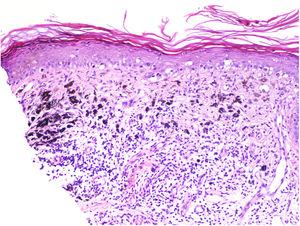

Se clasifica como «ausente» cuando no se identifica infiltrado o este existe pero no está en contacto con el tumor; «intenso» cuando el infiltrado infiltra completamente la base del tumor (fig. 1) o infiltra difusamente el tumor (fig. 2); por último, es «no intenso» cuando el infiltrado está en el tumor solo de forma focal o afecta a la base del tumor pero no en toda su longitud.

Además, se debe especificar si es intratumoral, peritumoral o ambos.